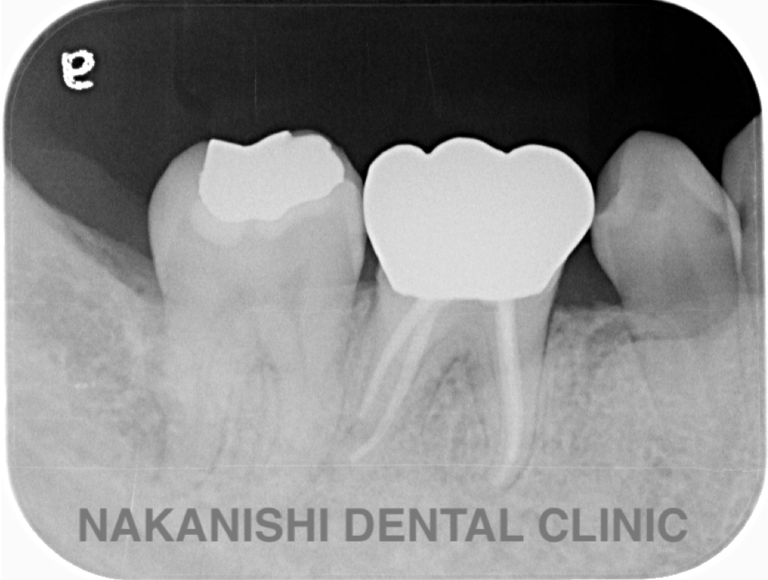

治療前

治療後

| 主訴 | 左下歯ぐきの腫れ。 |

|---|---|

| 治療期間 | 約2か月 |

| 治療費 | 約1万5千円 |

| 治療内容 | ラバーダム、マイクロスコープ下にて根管治療を施術。 歯ぐきの腫れ、痛みや違和感が消失したため根管充填、支台築造(土台の製作)を行った。治療後の写真は矯正治療を行うことになったため仮歯を装着した状態。 |

| 治療のリスク | マイクロスコープやCTを使用し、可能な限り精密な根管治療を行っていますが、歯根の形態や病変の大きさ、過去の治療履歴などにより、治癒が得られない場合があります。また、治療後に再感染や歯根破折が生じることもあり、その場合は再治療や抜歯が必要となることがあります。 治療結果には個人差があり、すべての症例で同様の経過を保証するものではありません。 |